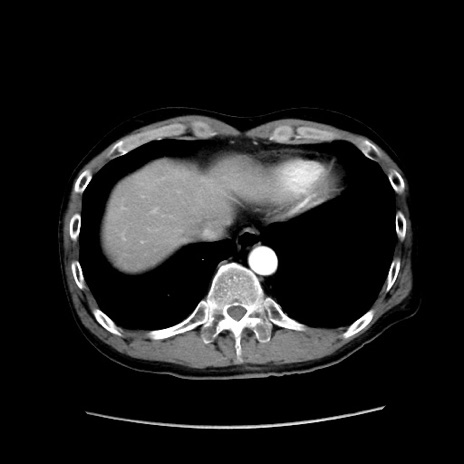

冠状断像

【症例】40歳代 男性

【主訴】腹痛

【現病歴】4時間ほど前に電車に乗車中に臍部上より腹痛出現。徐々に増悪し起立困難となり、救急外来受診。生ものは数日食べていない。今朝お雑煮を食べた。

【身体所見】BT 36.8℃、BP 117/84mmHg、HR 91/min、SpO2 97%、苦悶様、腹部:臍上部広範囲圧痛あり、反跳痛±

【データ】WBC 8100、CRP 0.03